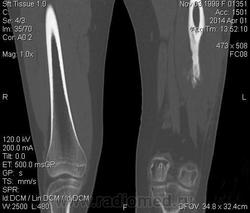

Молодая дама (14 лет) с переломом срдней трети диафиза левого бедра в анамнезе (декабрь 2012 г). Ломала ногу несколько раз в этом месте. Сейчас состояние после МОС. Как следует понимать изменения в кости, формируется ли ложный сустав?

Ох, не хочется думать о ложном суставе в 14 лет... По срокам под ложный сустав подходит, он характеризуется замыканием костномозгового канала с формированием подобий суставных поверхностей. У нее же есть хиленькая периостальная костная мозоль по задней поверхности бедра удерживающая отломки в правильном положении. Я склонна думать, что это скорее застарелый перелом (оно же замедленная консолидация). Здесь очень важно посмотреть предыдущие снимки (поиск рефрактуры, либо отсутствия полной консолидации).

Последнее слово все равно за ортопедами, здесь важнее функция, чем ломание копий ложный-не ложный. И я согласна с И.Бондаренко, хорошо бы чтобы оценили ортопеды подвижность под контролем рентгена.

Настоящего, родного ложного сустава пока нет, хотя костномозговой канал дистального отломка уже закрыт - образовалась склерозированная замыкательная пластина. Варусная деформация почти в 165 градусов... Я бы заключилась неполной консолидацией и варусной деформацией, прогностически формирование ложного сустава очень вероятно.